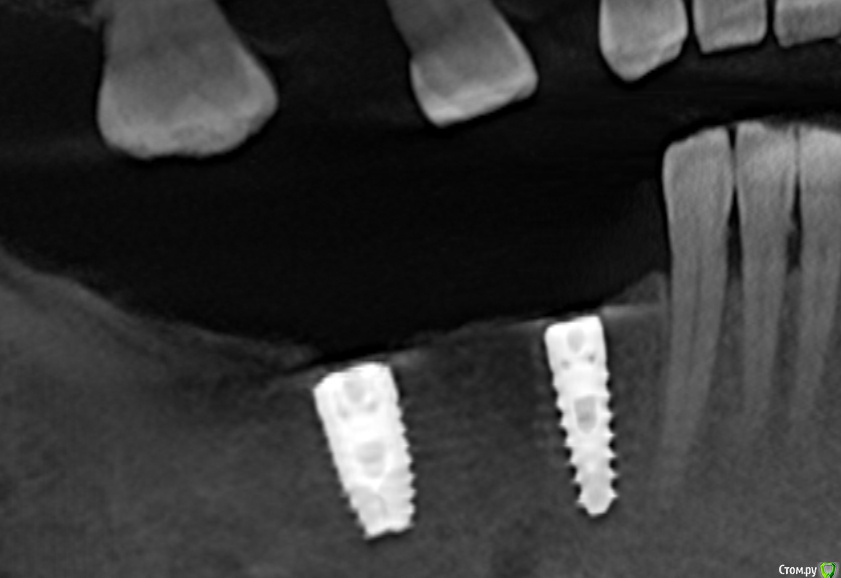

dentikl Опубликовано 13 декабря, 2019 Поделиться Опубликовано 13 декабря, 2019 С дистальным отличие в пару градусов, Запротезировать проблем не будет. Спасибо за совет.а можно увидеть срез ,чтобы попало оба импланта? Ссылка на комментарий

zumanok Опубликовано 18 декабря, 2019 Автор Поделиться Опубликовано 18 декабря, 2019 а можно увидеть срез ,чтобы попало оба импланта? Срез нормально выставить не получается на оба имланта. Прикреплю с панорамы Ссылка на комментарий

Bier Опубликовано 18 декабря, 2019 Поделиться Опубликовано 18 декабря, 2019 Слушайте, а реально пациентку беспокоит эта проблема? Ну стоит у вас имплантат в области сосочка, сделайте там керамический сосочек. Дискуссию развели как буд-то речь про центральный отдел с десневой улыбкой. 3 Ссылка на комментарий